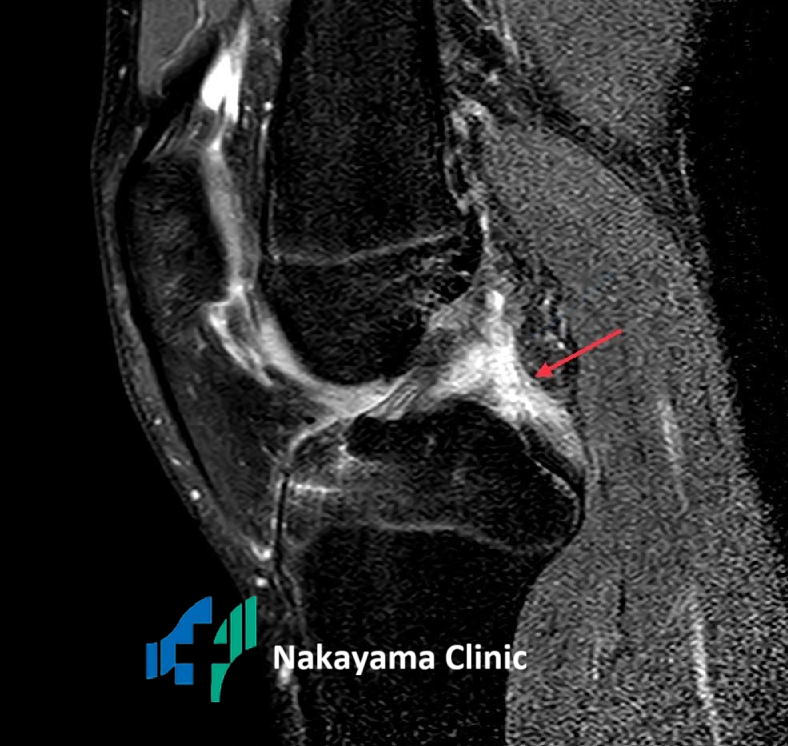

また、バイクや自転車での転倒、スポーツ中の転倒などで膝を曲げたまま強い衝撃を受けると、膝の安定を司る「後十字靭帯」が断裂し、膝の裏に強い痛みが出ます[3]。

黒い後十字靭帯が断裂して消失し白くなっている

Q2. 病院ではどんな検査をするの?

A2: 痛みの原因を正確に突き止めるために、いくつかの検査を行います。

👉 MRI検査: 軟骨や半月板、靭帯といった、レントゲンには映らない組織の状態を詳しく調べるのに非常に有効です。

これらの検査を組み合わせることで、あなたの「膝の裏が痛い」原因を正確に診断し、最適な治療法を見つけていきます。